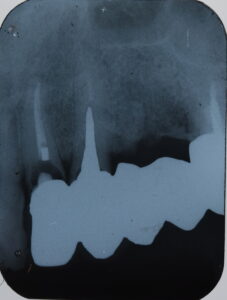

初診時。複数本のブリッジがグラついて食べ物が噛めないとのことでご来院されました。

レントゲン写真で精査すると、土台に大きな虫歯ができて、一部脱離していることがわかりました。

ブリッジを外してみると、そこには根の大きな虫歯と破折が見つかりました。これがグラつきの原因であったことがわかります。ブリッジを作り直すことはできず、歯は保存不可能と診断しました。いく通りかの治療方針の計画を立て、患者様との相談の結果、インプラント治療でしっかり噛めるようにする方針となりました。